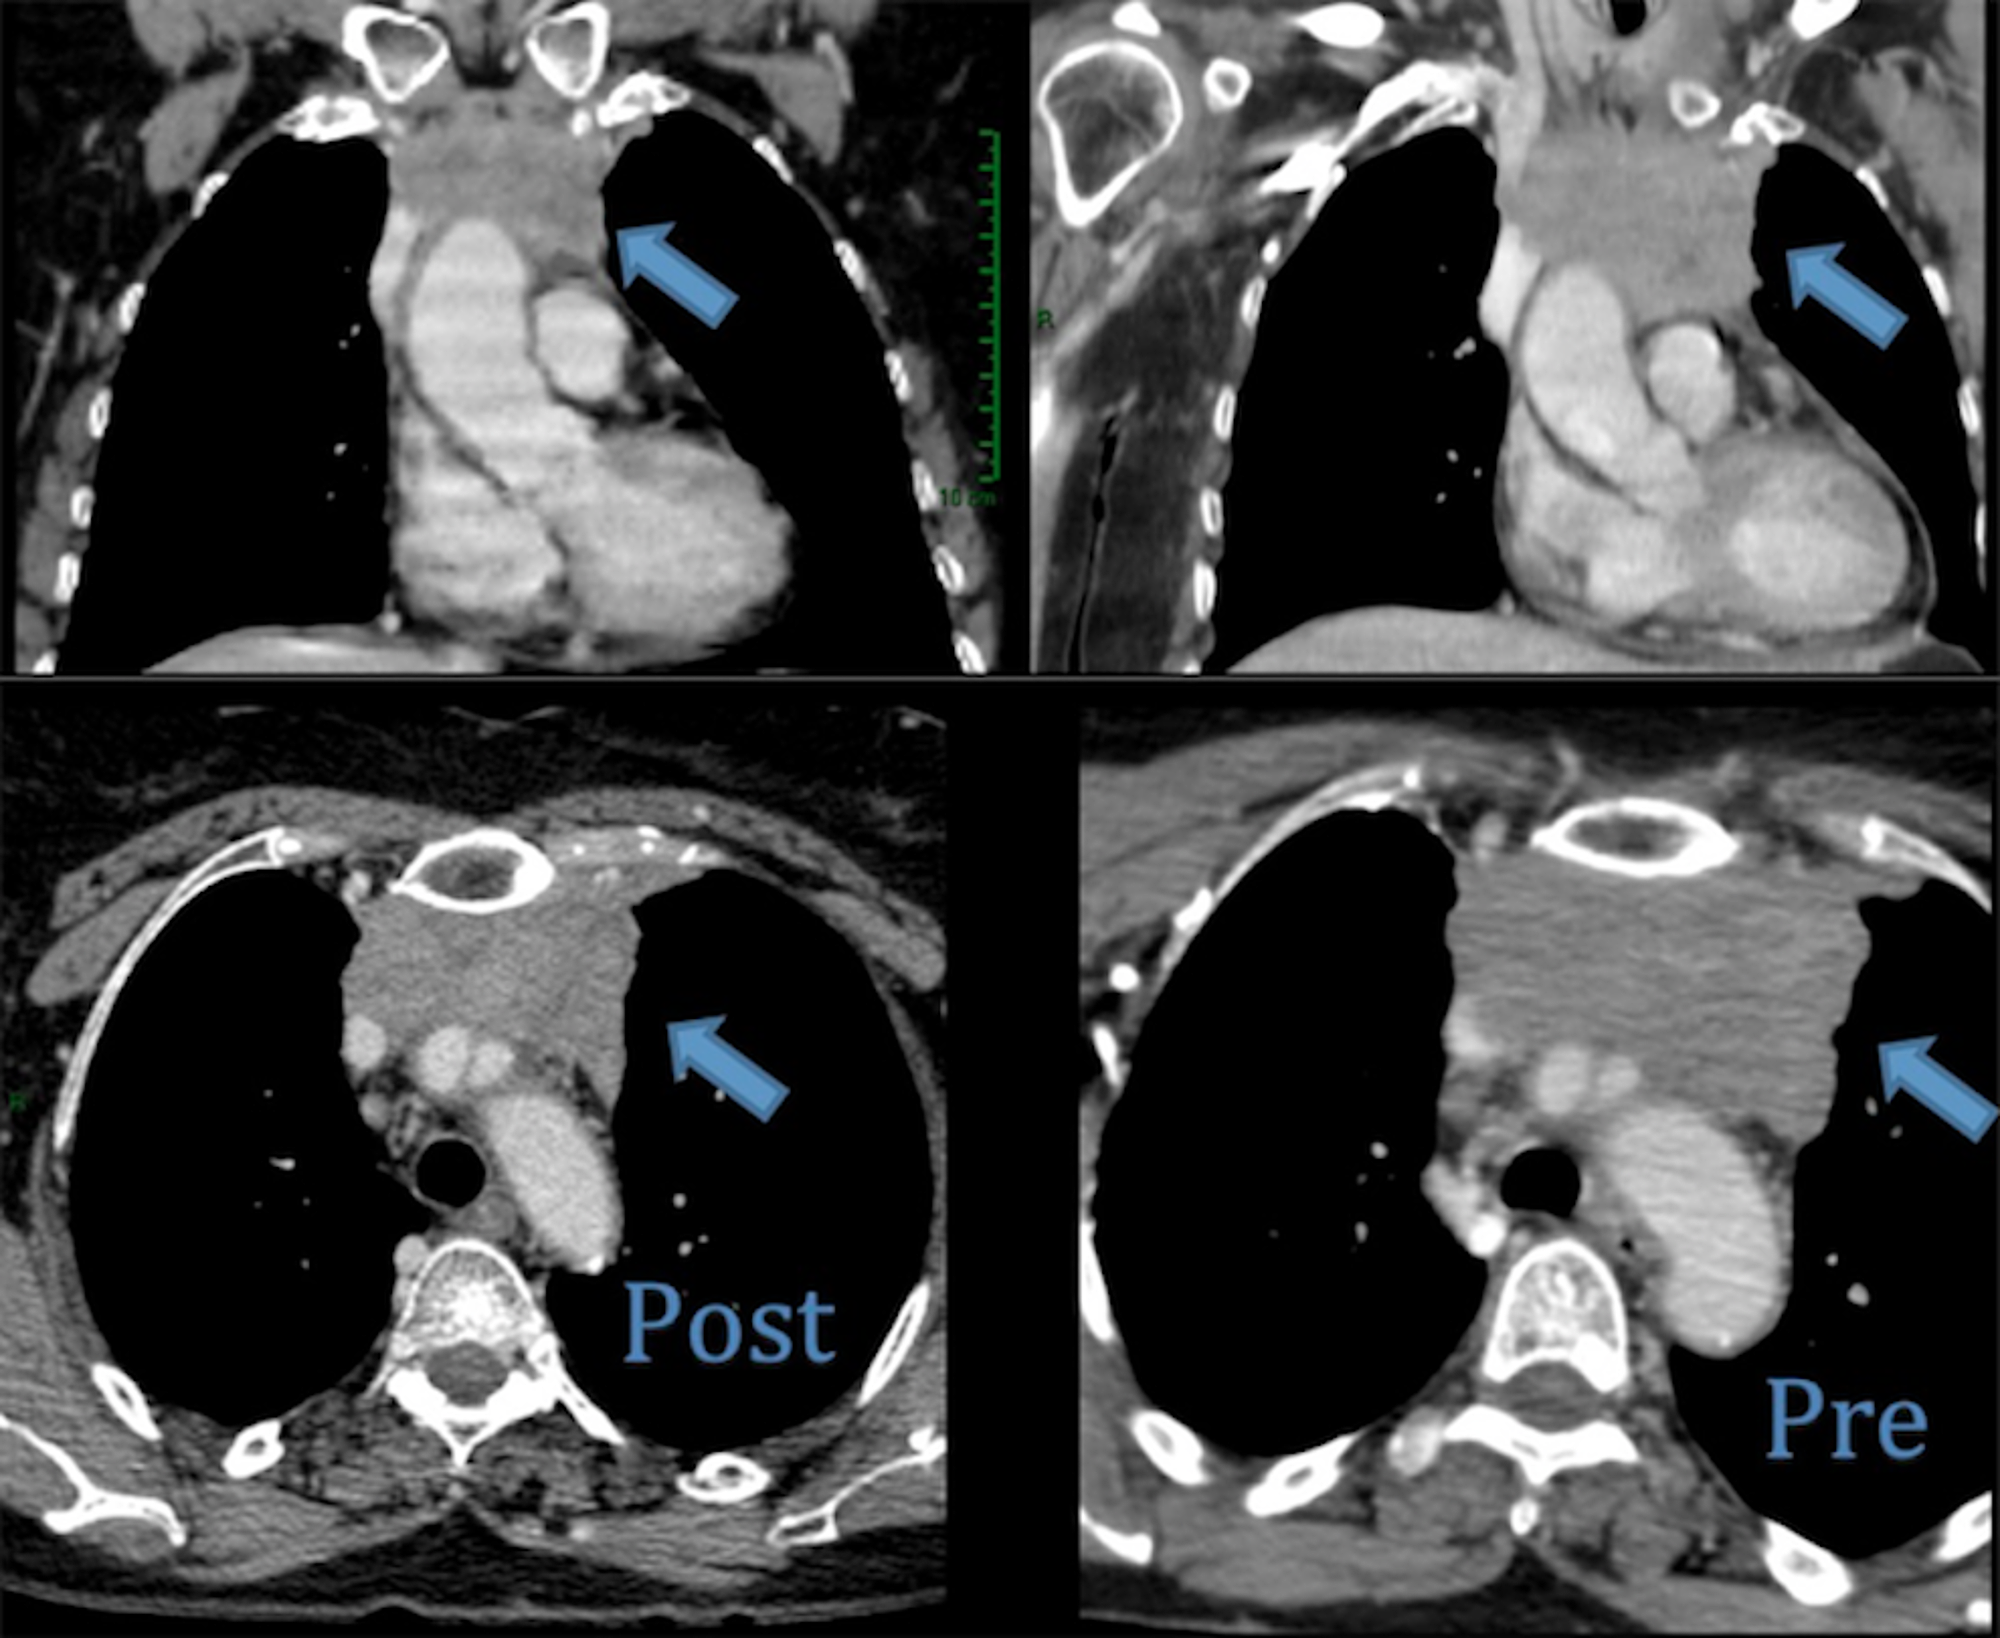

Cureus Metastatic Thymic Carcinoma with Long Survival After Treatment What Is Metastatic Thymic Cancer Numbers and letters after t, n, and m indicate more advanced disease. thymomas and thymic carcinoma are both thymic epithelial tumors (tets), but there are some important differences: thymoma and thymic malignancies occur when cancer cells form on the outer surface of the thymus. For example, if thymic carcinoma spreads. thymoma and thymic carcinoma treatment options include. What Is Metastatic Thymic Cancer.

Frontiers Imaging Evaluation of Thymoma and Thymic Carcinoma What Is Metastatic Thymic Cancer For example, if thymic carcinoma spreads. thymic carcinoma cells look very abnormal under a microscope. Numbers and letters after t, n, and m indicate more advanced disease. thymomas and thymic carcinoma are both thymic epithelial tumors (tets), but there are some important differences: the metastatic tumor is the same type of cancer as the primary tumor. For. What Is Metastatic Thymic Cancer.